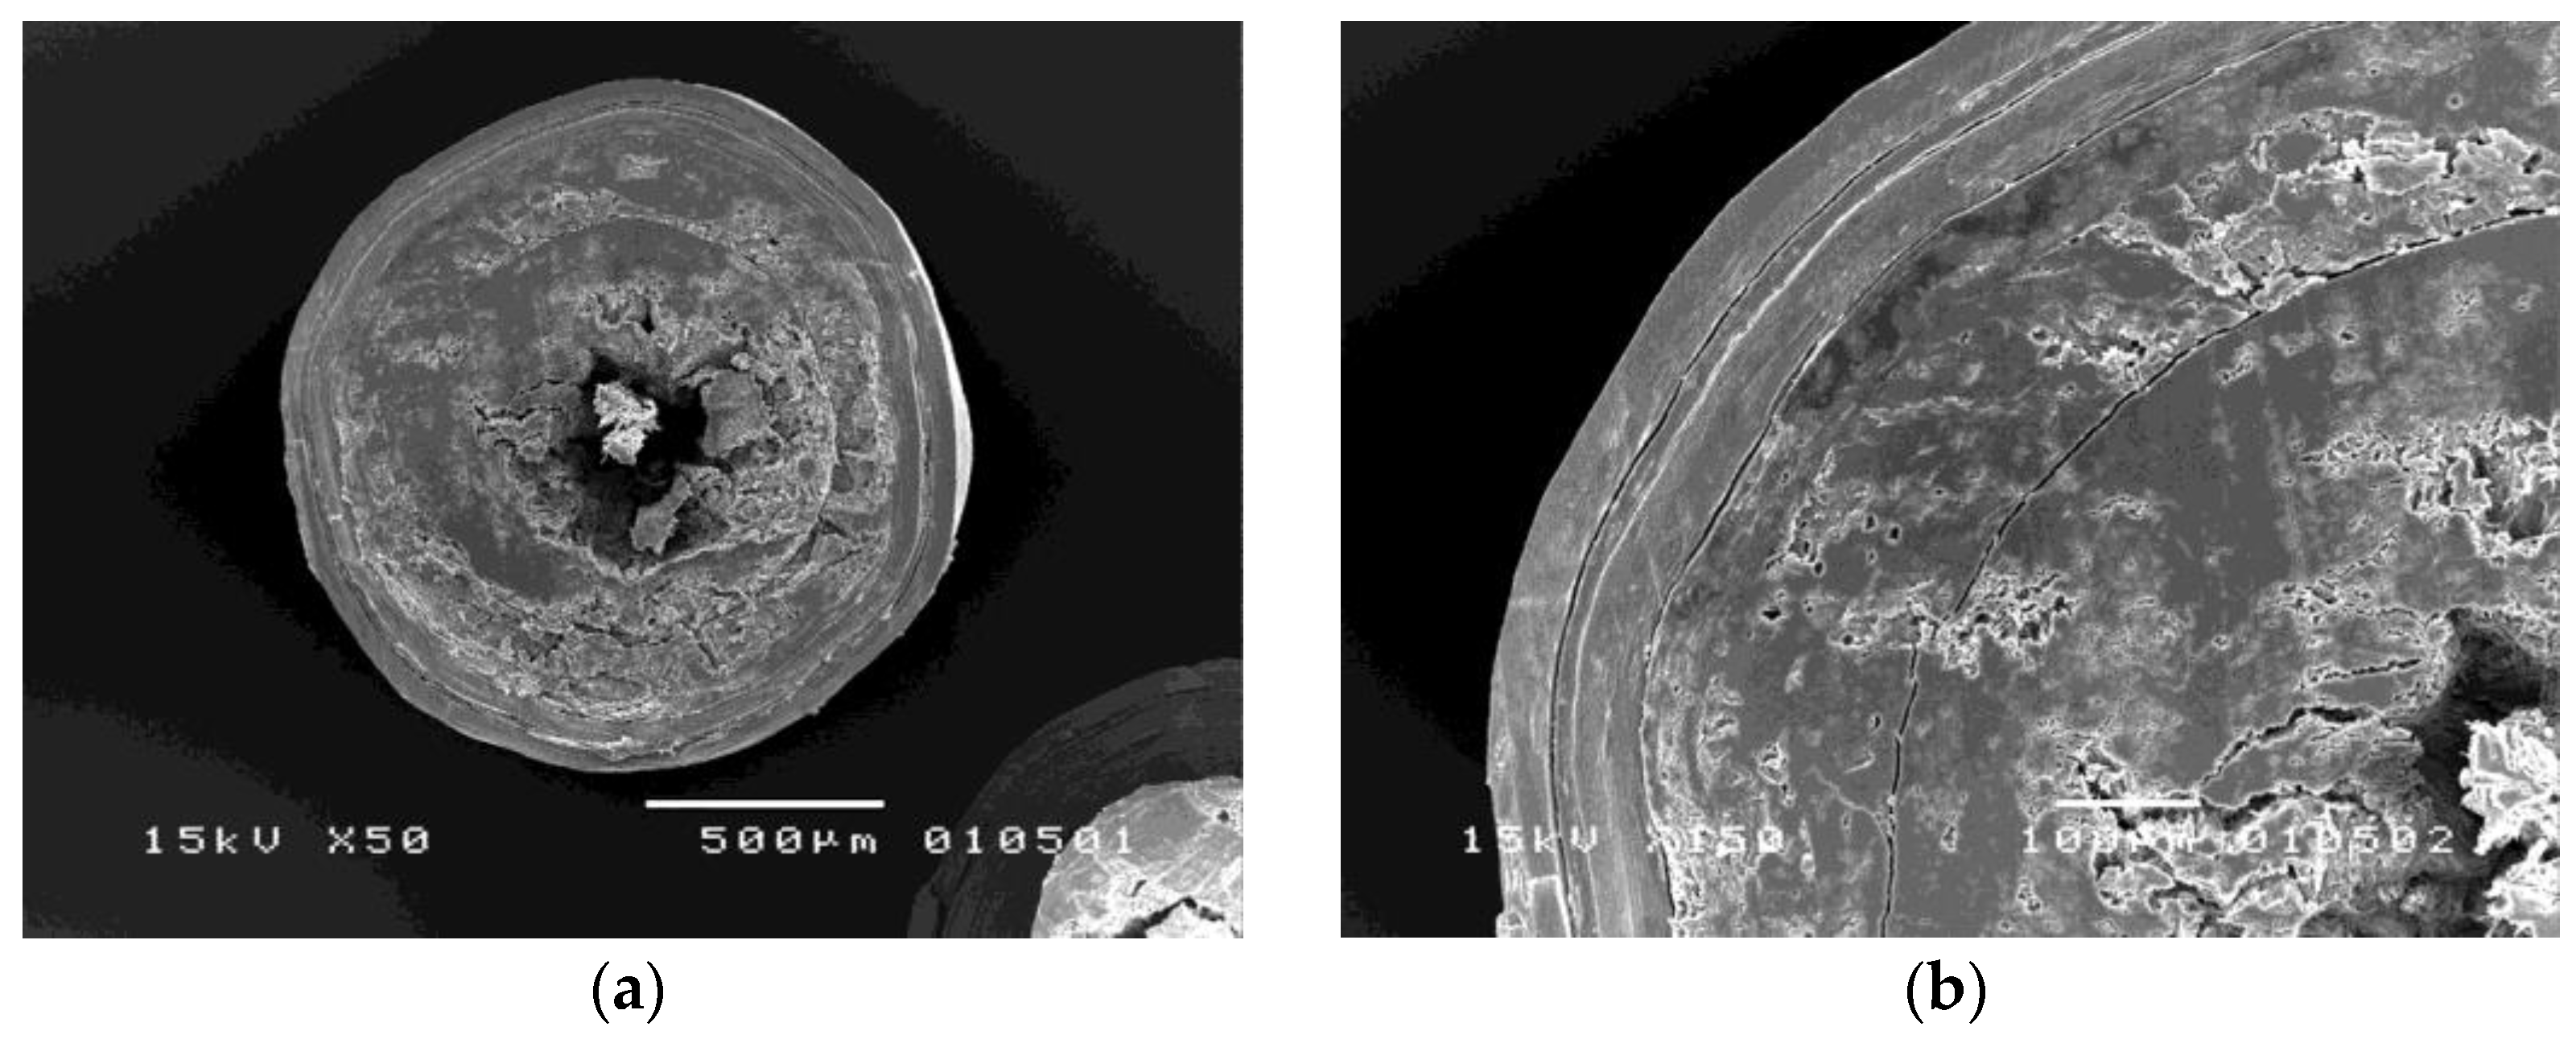

3.2.1. Morphology of Coated Metoprolol Tartrate Pellets